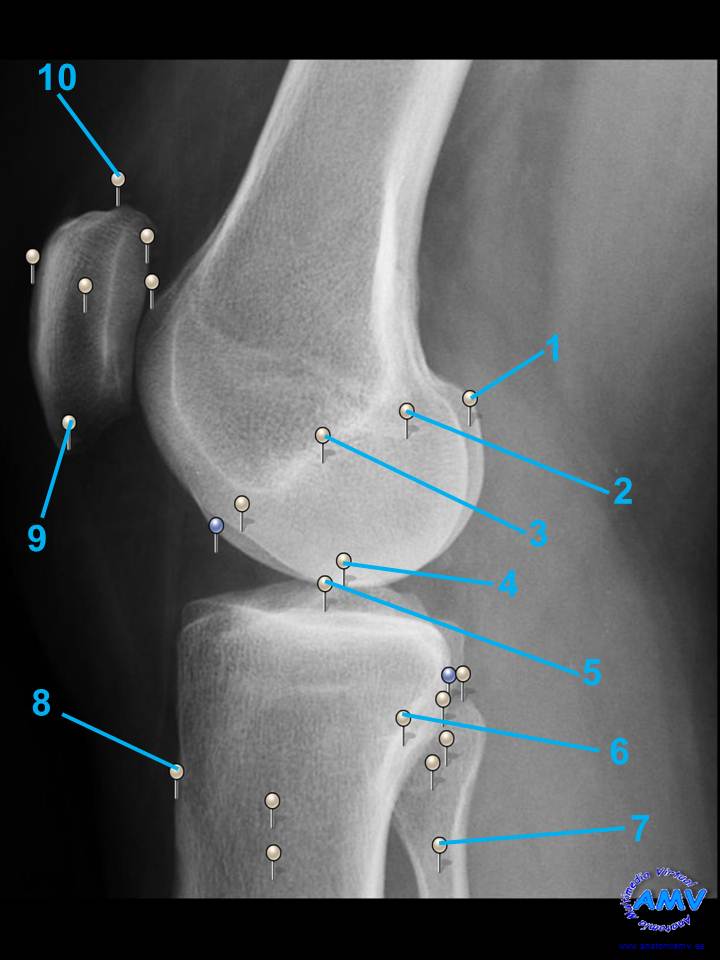

rx_mi_12.jpgIndique que estructura se señala con el número correspondiente:

El nº 1 señala .

El nº 2 señala .

El nº 3 señala .

El nº 4 señala .

El nº 5 señala .

El nº 6 señala .

El nº 7 señala .

El nº 8 señala .

El nº 9 señala .

El nº 10 señala .